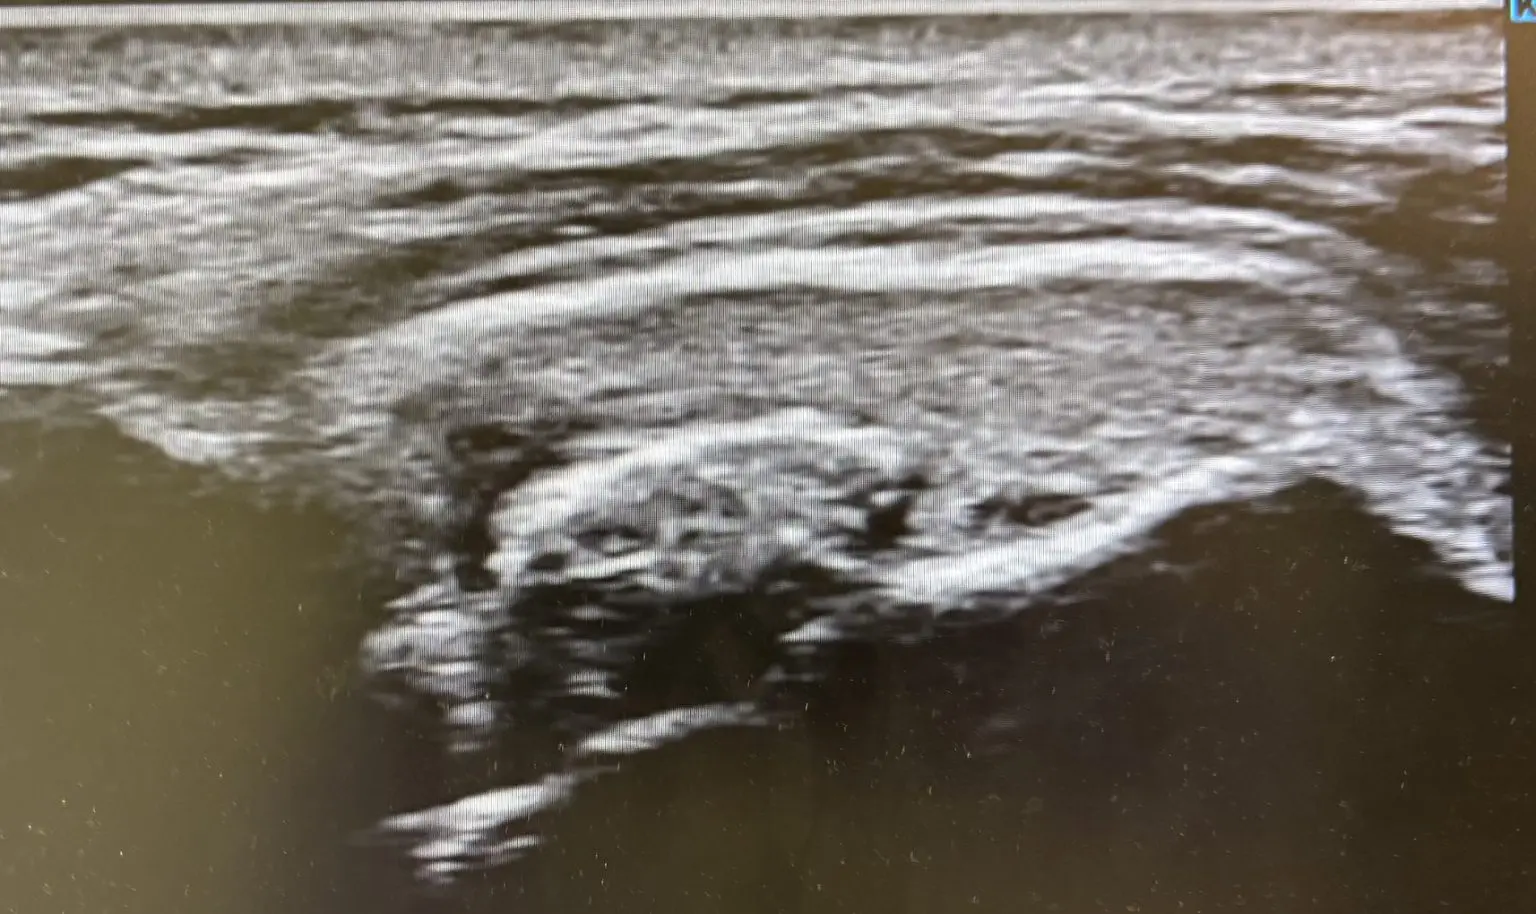

- 腱板(肩の深い筋肉)の損傷の有無

レントゲンでは骨しか映らないため「異常なし」と言われてしまうこともありますが、エコーなら筋肉・腱・靭帯のトラブルをその場で把握できます。しかも動かしながら観察できるため、「どの角度で引っかかるか」まで再現できるのが大きな利点です。

「四十肩」「五十肩」という言葉はよく耳にしますが、実は肩の痛みにはさまざまな原因があります。肩を動かす筋肉(腱板と呼ばれるグループ)の損傷、炎症による関節包の硬さ、石灰が沈着して急に激しい痛みを引き起こすこともあります。

レントゲン検査では骨の状態は分かりますが、筋肉や腱、靭帯の状態までは映し出せません。そのため「異常なし」と言われても、実際には肩が痛くて腕が上がらない、ということが起こり得るのです。